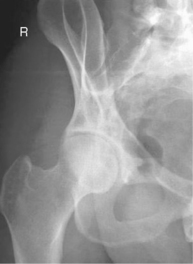

• For femoral neck, flex affected knee and hip, and abduct femur 45° from vertical (places femoral neck near parallel to IR).

• For femoral head, acetabulum, and proximal femoral shaft, oblique patient 35°–45° toward affected side and abduct leg to tabletop if possible. Center hip and neck area to CR.